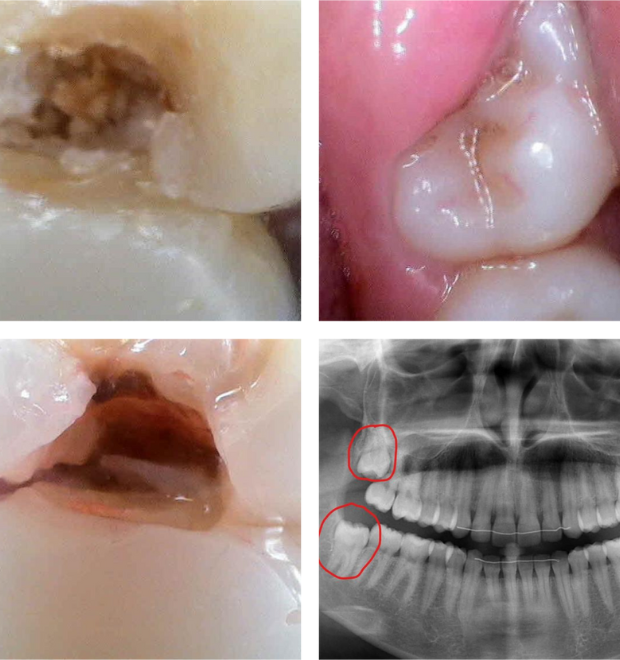

✅ Comprehensive Diagnosis – Digital X-rays to assess the position of the tooth.

✔ Impacted or Partially Erupted Teeth – Can cause pain and infection.

✔ Gum Inflammation & Infection – Due to trapped food and bacteria.

✔ Difficulty in Cleaning – Increasing the risk of cavities and gum disease.